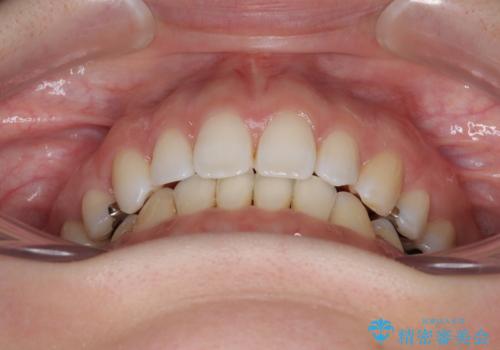

- 口元の突出感と口の閉じにくさを気にして来院された患者様です。

上下左右第一小臼歯4本を抜歯し、ワイヤー装置にて口元を引っ込めるよう矯正治療を行うこととしました。

奥歯が前方に傾斜していることで深く咬みこむ(ディープバイト)状態であったので、なかなか抜歯したスペースが閉じず、様々な方法でディープバイトを改善しながら治療を進めていくこととなりました。